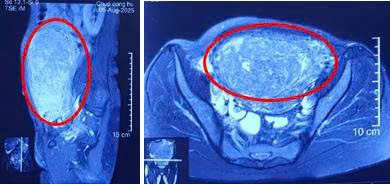

MRI bụng cho thấy khối choán chỗ lớn khả năng xuất phát từ thân tử cung, lan lên vùng bụng phải; xâm lấn khoang sau phúc mạc, đại tràng ngang bên phải kế cận.

Hình 1. Hình ảnh khối u (trong đường viền đỏ) trên phim MRI chiếm hết khoang bụng, chèn ép đẩy lệch cơ quan khác trong ổ bụng